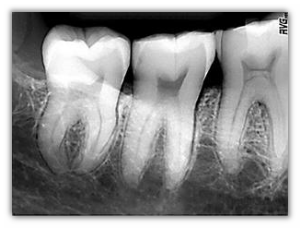

Nuovo design del sensore. Con il sensore di dimensione 1 l'immagine ha una superficie più larga del 10%. L'inquadratura dei denti da radiografare è più facile ed il confort visivo superiore. Il sensore di dimensione 1 permette così di riprendere due molari su una stessa lastra periapicale e può anche essere utilizzato in posizione orizzontale quando il palato è poco profondo (es. nei bambini). Gli angoli del sensore sono stati ulteriormente arrotondati in modo che risulti più confortevole in bocca e permetterne un posizionamento più facile.